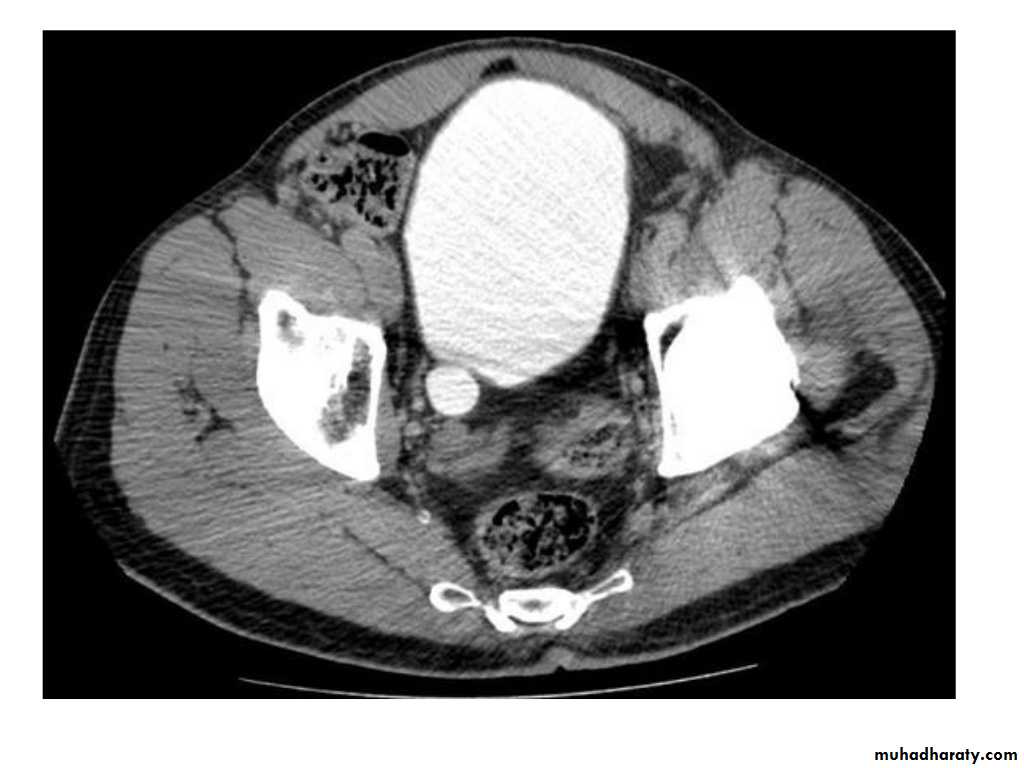

IVU shows

1. The kidneys at low position .2.Close to the spine with long axis parallel to the spine

3. Malrotation manifested by medially directed calyces.

4- The renal pelvis and ureters are anterior and lateral in position.

5- Hydronephrosis and calculi highly associated.